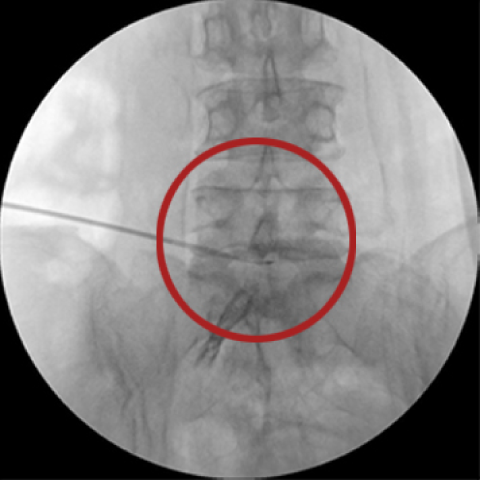

풍선 확장술

기존의 신경성형술과 비슷하지만 풍선확장 기능이 추가, 꼬리뼈를 통해 특수 관(카테터)을 병변 부위에 삽입하고, 카테터 끝의 풍선(실리콘)을 확장시켜 좁아진 척추관을 넓혀 약물을 주입시켜 효과적으로 통증을 치료하는 방법

풍선성형술 시술 과정

1. 꼬리뼈 부위를 통해 풍선이 내장되어 있는 특수 카테터 삽입

2. 영상증폭장치(C-arm)을 통해 좁아진 척추관에 카테터 삽입

3. 병변부위를 도달시킨 후 좁아진 척추관에 풍선을 부풀려 신경관 공간을 넓힘

4. 넓어진 신경관에 특수 약물 주입

5. 염증 제거 및 만성 통증 감소